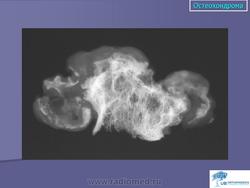

Хондросаркома нередко появляется в центральных частях скелета, таких как кости таза, плечевые кости и ребра. Светло-клеточный вариант склонен к росту в эпифизах длинных трубчатых костей. В противоположность энхондроме хондросаркома редко поражает дистальные отделы конечностей. Как правило, эта опухоль болезненна и весьма быстро растет. Узловой вариант роста хряща сопровождается рентгенологически заметным внутрикостным фестончатым рисунком. Медленно растущая хондросаркома низкой степени злокачественности приводит к реактивному истончению коркового слоя, в то время как более агрессивная опухоль высокой степени злокачественности разрушает корковый слой и формирует мягкотканную массу. Обызвествленный матрикс выглядит на рентгеновских снимках в виде хлопьевидных рентгеноплотных участков.

Основной вариант хондросаркомы состоит из малигнизированного гиалинового и миксоидного хряща. Крупная опухоль построена из узлов, сформированных серовато-белой, частично полупрозрачной блестящей тканью. В преимущественно миксоидных вариантах ткань опухоли вязкая, студенистая и как бы стекает с поверхности разреза. Весьма типично наличие пятнистых кальцификатов, а зоны некроза в центре опухоли могут превращаться в кистозные полости. Прилежащий корковый слой утолщен или эрозирован, опухоль растет с обширным «фронтом давления» в окружающие мягкие ткани. Малигнизиоованный ХРЯЩ инфильтрирует костномозговую полость и костные балки. В зависимости от степени гистологической дифференцировки в ткани новообразования варьирует уровень целлюлярности, клеточной атипии и митотической активности. При низкой степени злокачественности (1-я степень) и высокой степени дифференцировки отмечается гиперцеллюлярность, хондроциты содержат набухшие пузырьковидные ядра и небольшие ядрышки. Изредка встречаются двуядерные клетки, фигуры митоза выявляются с большим трудом. Весьма характерна очаговая минерализация матрикса, хрящ может подвергаться энхондральной оссификации. При 3-й степени злокачественности низкодифференцированная хондросаркома характеризуется выраженной гиперцеллюлярностью и крайним полиморфизмом с причудливыми гигантскими опухолевыми клетками. Фигуры митоза обнаруживаются легко. Хондросаркомы 3-й степени злокачественности встречаются редко. Атипичный хрящ чаще всего является компонентом хондробластической остеосаркомы.

"Хрящевая матрица"